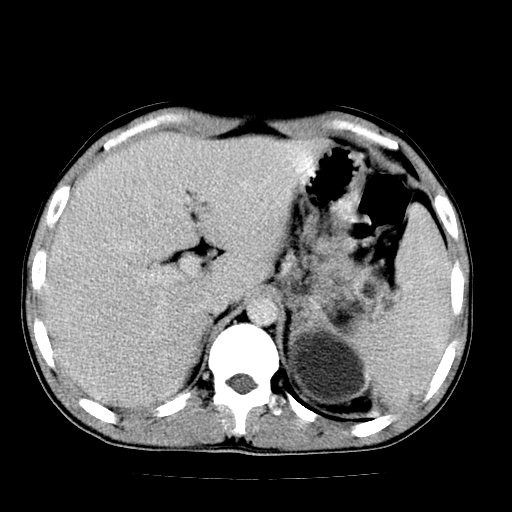

以下是引用天南地北在2007-4-30 13:36:00的发言:[br]支持慢性胰腺炎伴有假性囊肿

以下是引用andymaomao在2007-4-30 14:28:00的发言:[br]支持:1.慢性胰腺炎并假性囊肿形成可能;[br] 2.左肾形态稍增大,旋转不良。